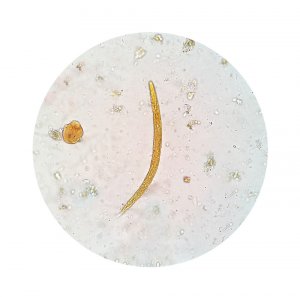

The specific cause of amoebic dysentery is a microorganism called Endameba histolytica. This organism is spread throughout the body with feces and is transmitted to other people when it contaminates food or water. It affects the mucous of the intestines, especially the large intestine.

Any infection that is caused by organisms that presents amoebic dysentery is called amebiasis. However, it’s only called this when there are symptoms, especially diarrhea. Many people are infected without knowing it because there are no symptoms.

The true nature of the infection is easily determined with an analysis of fecal matter. This will discover if there are active amoebas or cysts.